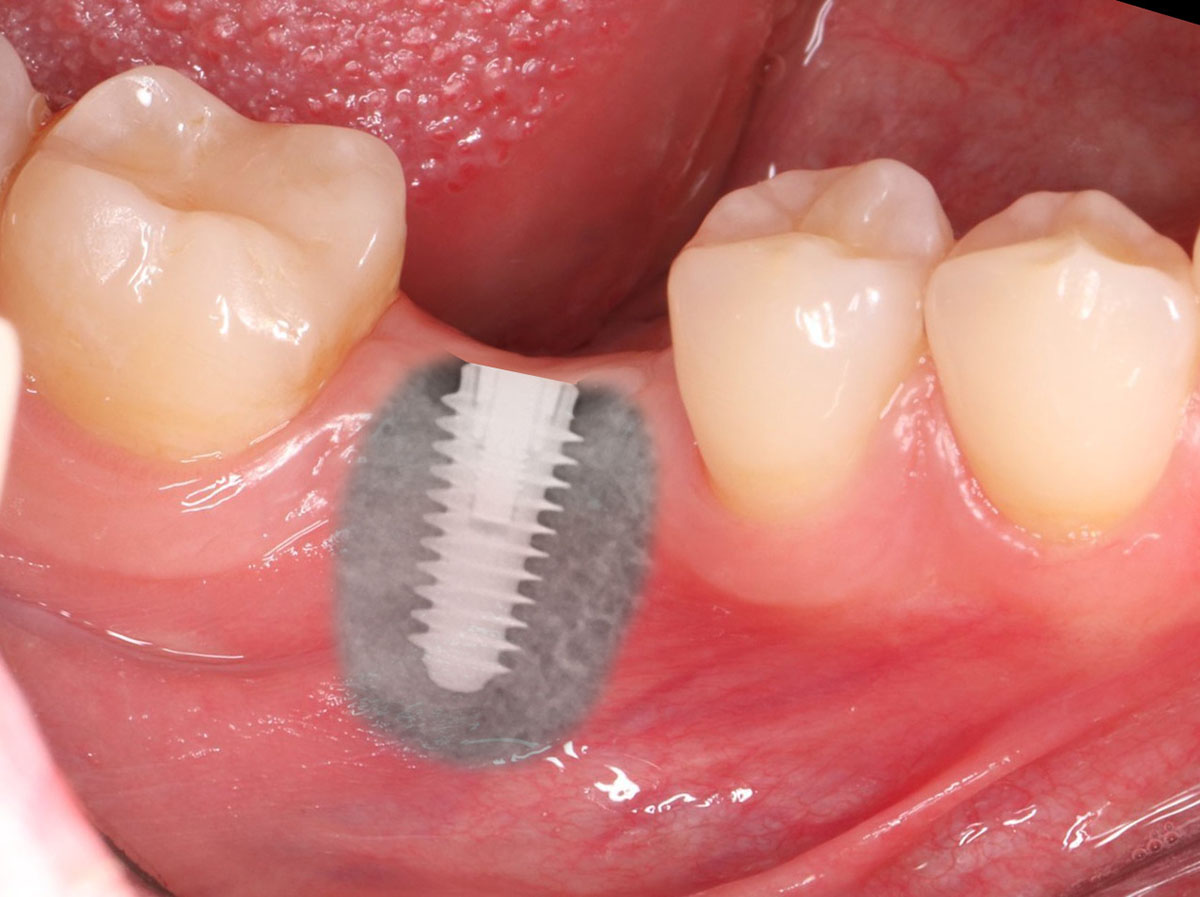

Протокол All-On-6 дозволяє встановити 6 імплантів, два з яких – у передній відділ щелепи, а чотири – у жувальний. Це зменшує потребу у кістковій пластиці, навіть при недостатності кісткової тканини, і дозволяє провести імплантацію за один прийом.

При дефіциті кісткової тканини можливе уникнення пластики та нарощування. Імпланти закріплюються під кутом, що дозволяє не торкатися гайморових пазух.

У рамках однієї процедури пацієнту видаляють зуби, що залишилися, і відразу встановлюють 4 імпланти. Операцію проводять під анестезією або уві сні (за бажанням пацієнта), приблизно за 1,5 години. 3D моделювання дозволяє встановити імпланти в точно підібране місце кісткової тканини. Тоді відновлення відбувається легше і швидше.